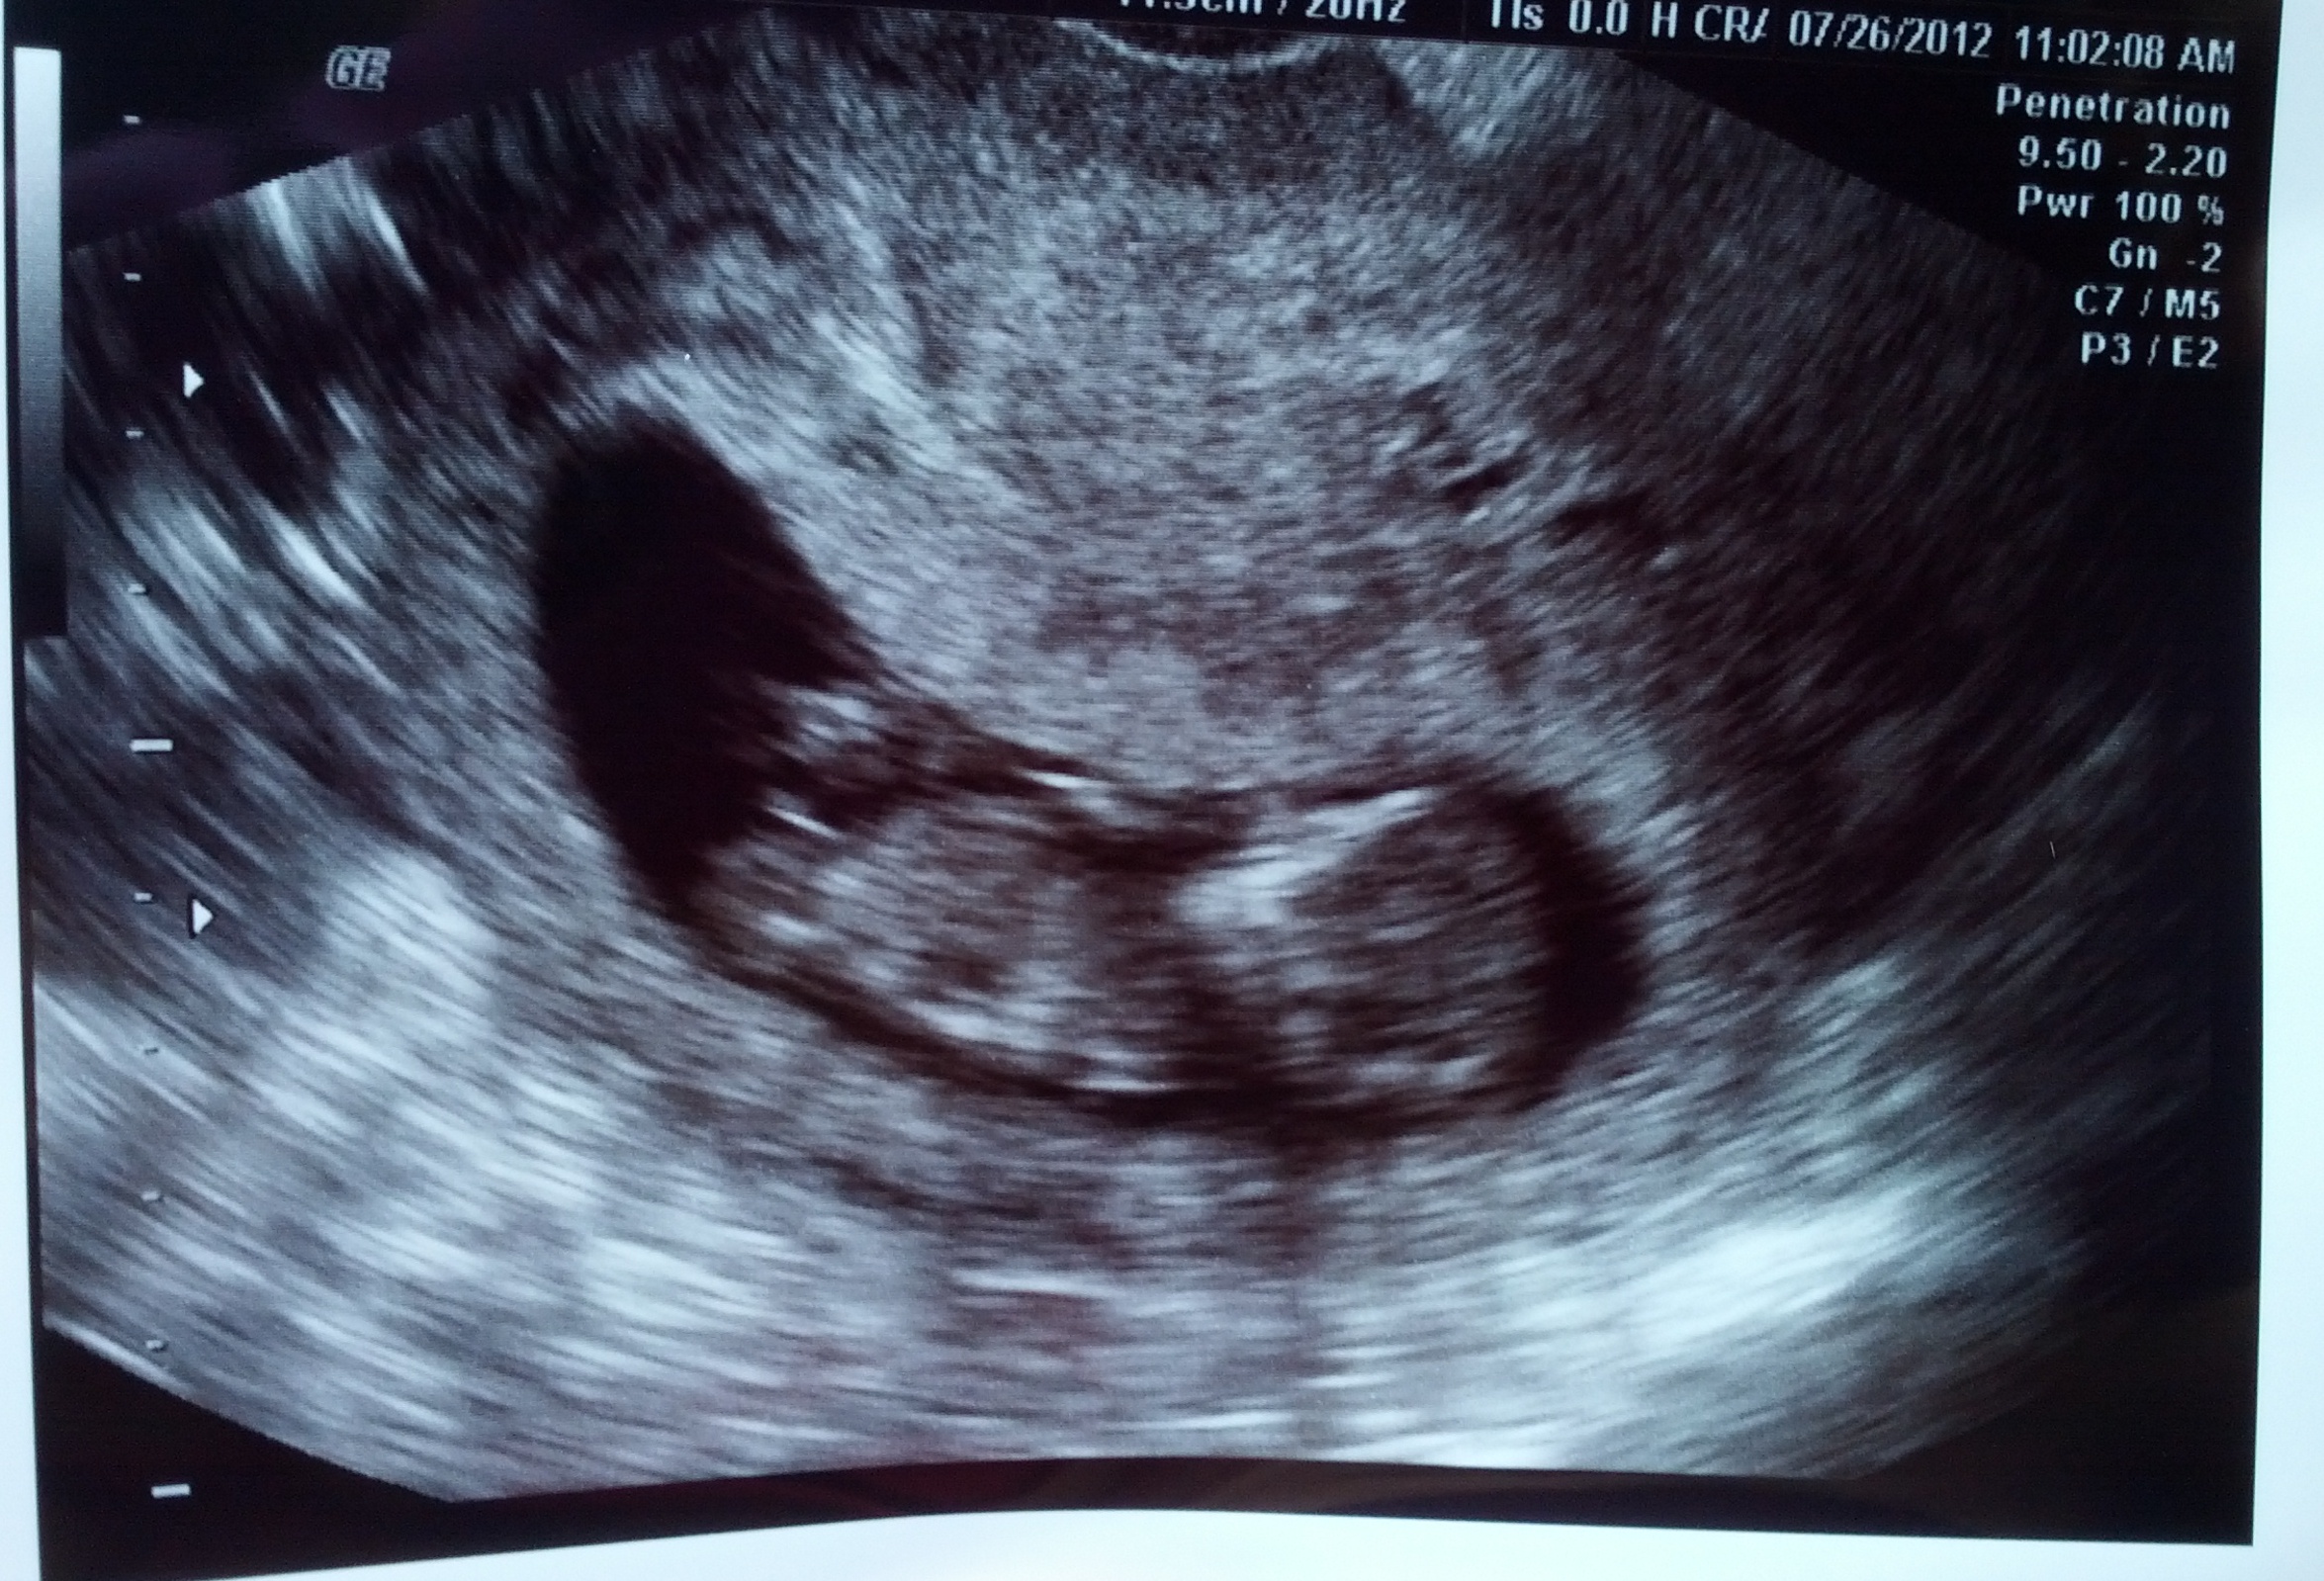

The tech told me the baby was not in profile view...but I've had a couple people tell me they think it is in profile. The nub is very visible, but I"m not sure if it's a reliable position to guess from? Please give me your honest opinions of what direction the baby is facing and whether a nub guess is possible...Thank you!!!

Attachment 3945

Attachment 4417